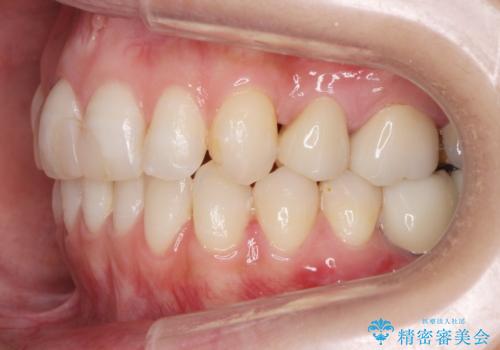

あきらめないで!!虫歯でボロボロでも大丈夫! 非抜歯矯正と虫歯、インプラント治療で見違える歯並びに。

途中矯正後に妊娠出産、育児等で2年以上中断を経た後虫歯治療の続きを行いました。最終的に治療完了まで行い状態は安定しています。